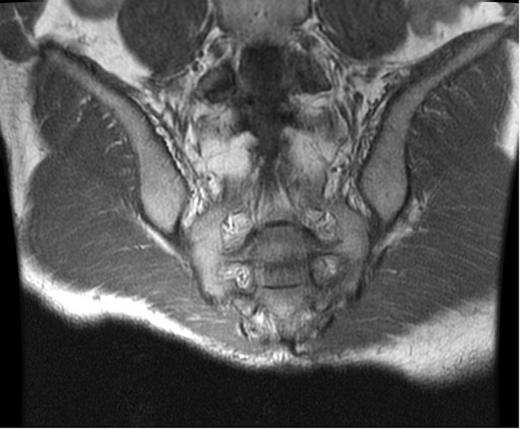

At the time of evaluation at our institution, he was afebrile and the laboratory tests, including inflammatory markers, were unremarkable. A computed tomography (CT) scan of the abdomen and pelvis showed a presacral fluid collection with a fistula between the pouch and the sacrum (Fig. 1). An MRI of the pelvis was performed and this revealed signs of osteomyelitis involving the S2–S4 vertebrae (Fig. 2). A laparotomy was performed and the ileal-anal pouch anastomosis was taken down, the sacrum was debrided leaving a large anterior bony defect. No omentum was available, so a 10 cm × 10 cm piece of Alloderm was used to cover the defect. The pouch fistula was excised and closed and the revised pouch re-anastomosed to the anus. The patient made an uneventful recovery and was discharged on the seventh postoperative day. Cultures from the sacral debrided tissue yielded Actinomyces spp. and a 12-week course of antibiotics (clindamycin) was commenced.

CT scan. Presacral air-fluid collection with a pouch-sacral fistula (arrow).